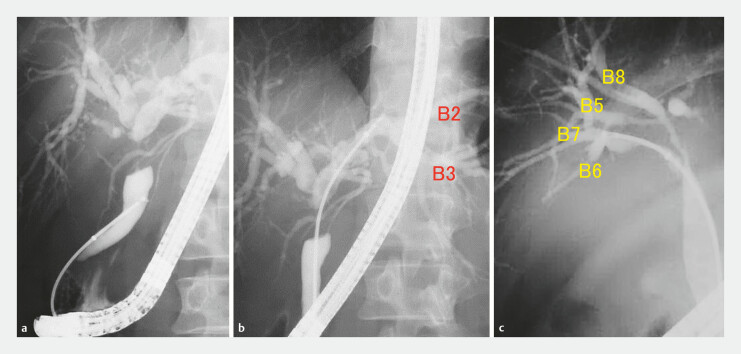

Background and study aims: Preoperative evaluation of biliary tract cancer progression plays a critical role in assessing resectability and in selecting the appropriate surgical procedure. This study aimed to evaluate the utility of a novel tapered-tip sheath system for mapping biopsy to assess the extent of biliary tract cancer.

Patients and methods: This observational, comparative study included 32 patients who were diagnosed with biliary tract cancers and underwent mapping biopsies with the novel tapered-tip sheath system and 21 patients using the conventional methods before the period. Technical success, total biopsy time, number of biopsy specimens, appropriate tissue sampling, adverse events (AEs), and negative surgical margin in case of surgical resection were evaluated.